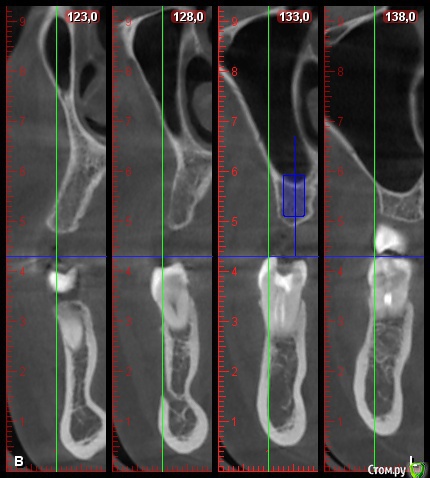

DenisV Опубликовано 12 мая, 2018 Поделиться Опубликовано 12 мая, 2018 (изменено) Уважаемые коллеги помогите начинающему имплантологу, в области 2.6 ЗСЛ, в области 2.4 как лучше поступить? расщепление + сст, или НКР? Изменено 12 мая, 2018 пользователем DenisV Ссылка на комментарий

DenisV Опубликовано 12 мая, 2018 Автор Поделиться Опубликовано 12 мая, 2018 ширина гребня в области 2.4 - 4мм Ссылка на комментарий